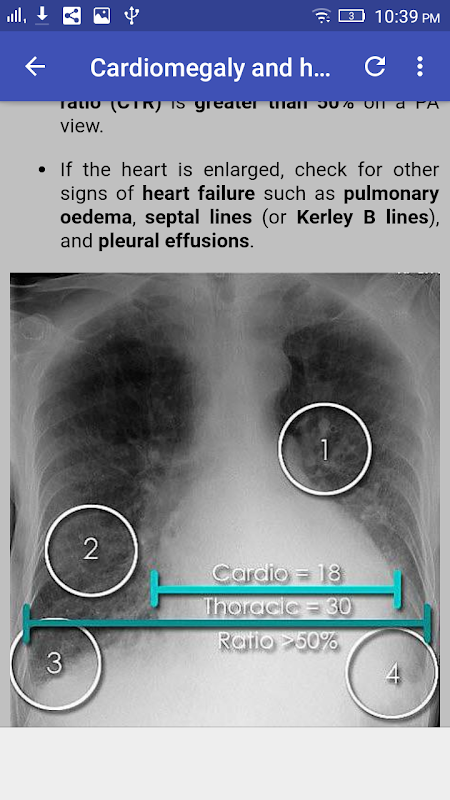

• 5 Schermata Chest X-Ray Interpretation

• 6 Schermata Chest X-Ray Interpretation